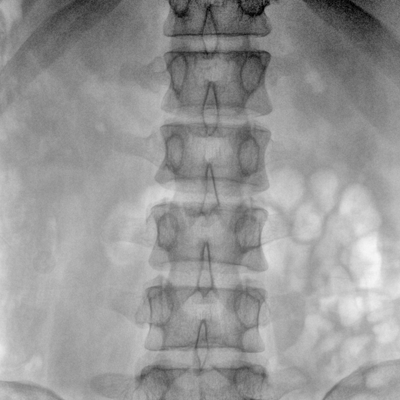

大尺寸動(dòng)態(tài)平板探測(cè)器,高DQE、低噪聲、圖像清晰。采用多分辨率圖像增強(qiáng)處理技術(shù),不同部位不同圖像處理算法,滿足客戶多樣化的需求。

采用智能變頻脈沖透視技術(shù),優(yōu)化圖像質(zhì)量的同時(shí)降低輻射劑量,呵護(hù)醫(yī)患健康